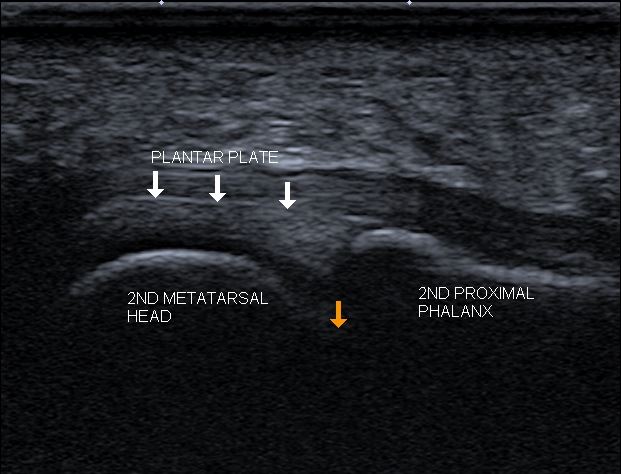

A podiatrist can diagnose a plantar plate tear by performing a physical examination and taking a medical history. Imaging tests like diagnostic ultrasound and MRIs may also be used to confirm the diagnosis and determine the extent of the injury.

Diagnostic ultrasound is performed to check the quality of the plantar plate.